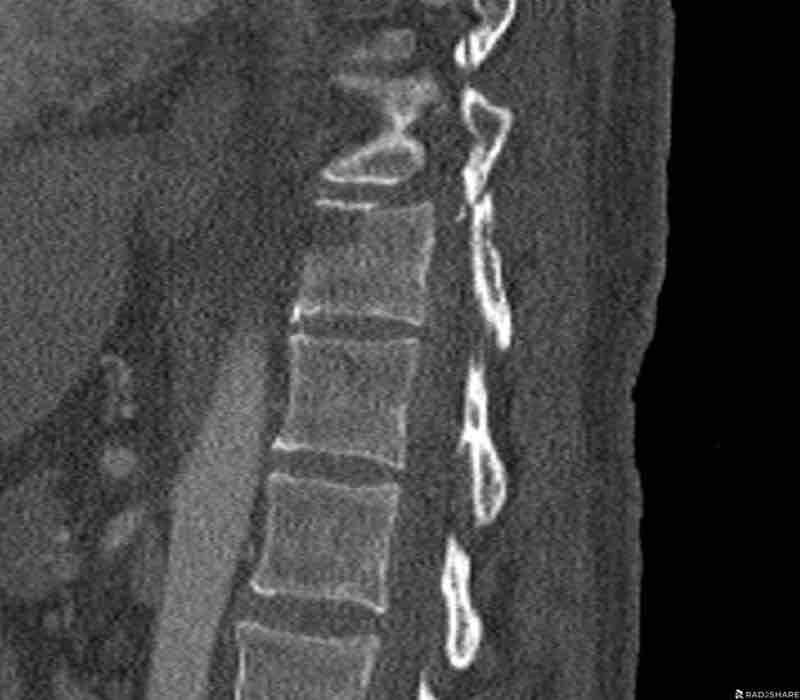

Scroll through images.

What are the findings?

Findings

- C injury? No.

- Signs of a rigid spine?

Yes, a B3 injury is very likely. - A subtle fracture on the anterior vertebral body.

Conclusion

Injury type B3.